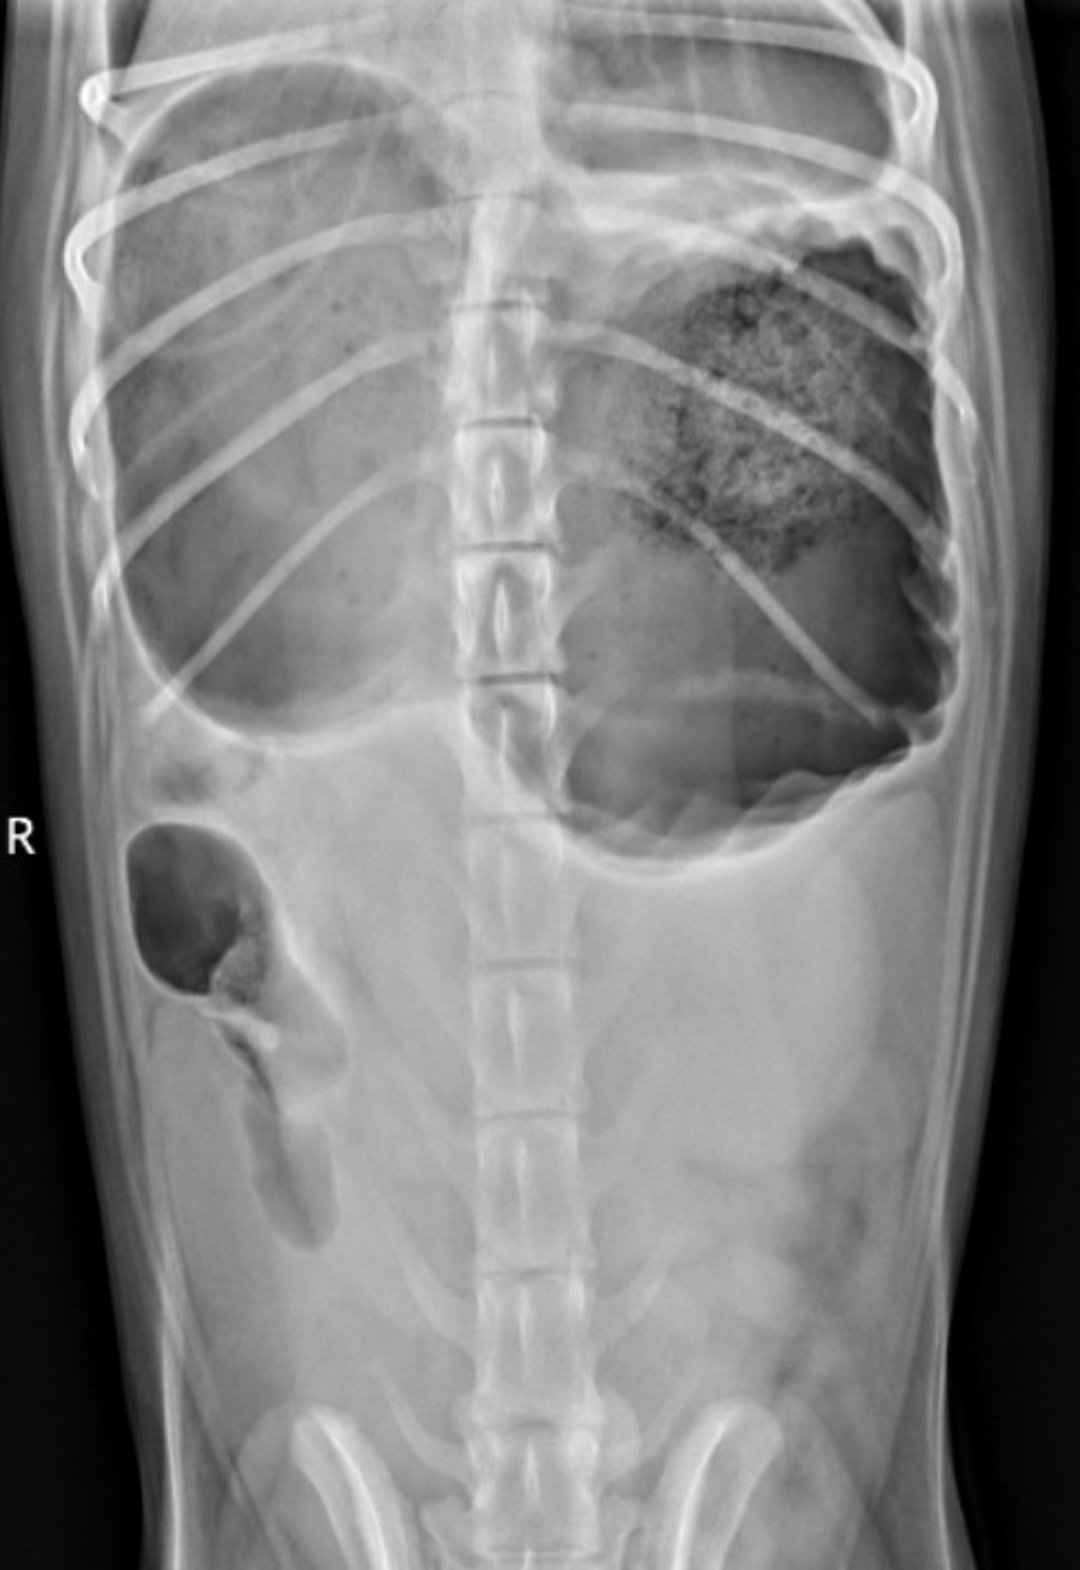

Ventrodorsal radiograph showing the "double bubble" in an 18-month-old Standard Poodle with gastric dilation and volvulus.

Double bubble radiograph, ventrodorsal view, dog